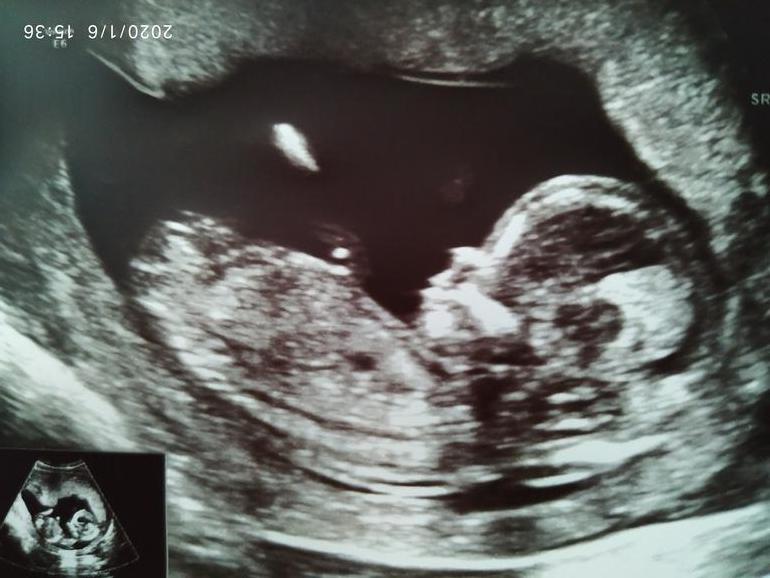

УЗИ в 13 недель.

Это скорее всего пуповина. Уж очень большое для 13 недель

Насколько вычитала на ББ, на Вашем сроке тут важно не то, что там виднеется меж ног, а то, какой угол оно принимает, когда смотришь сбоку🤔

Богатырь ведь! У девочек пирожочек совсем по другому выглядет, он прям между между ножек внутри и совсем вперёд не выпирает. Ну по крайней мере У нашей так разглядели два узиста.

И профиль какой мужественный, подбородок💪

Увидела первую фотографию и первая мысль - мальчик! 😀 у нас такой же пистолетик был, что 13,1 без сомнений увидели мальчика 😊

На сколько я знаю на этом сроке гениталии еще малоразличимы. Но врачу виднее, наверное..

Так не большое, это нога согнута и стопа между ног :) а пол не очень пока видно. Недели через 2 точно уже будет видно.

Если честно, мне видится девочка. 2 полосочки это губы и поменьше клитор. А на фото в профиль бугорок не видно,клитор длинный в этом сроке и можно спутать с пенисом.

Половой бугорок Мальчик девочка?